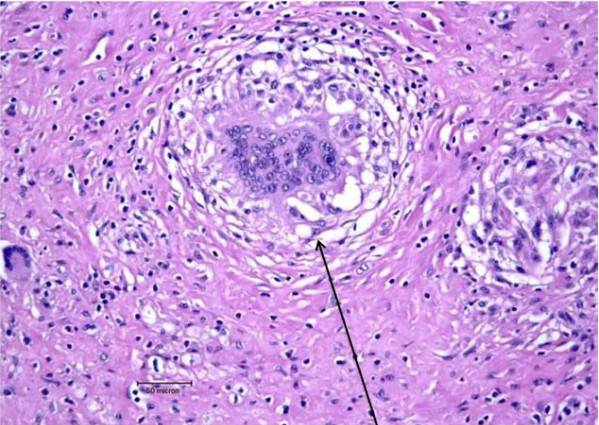

结节病(sarcoidosis)是一种病因未明的多系统肉芽肿性疾病(见图 1),临床上以双侧肺门淋巴结肿大,肺浸润及皮肤、眼睛损害为主要表现,肉芽肿结节可侵犯全身各器官。心脏肉芽肿指的是心肌里面发生肉芽肿性炎。影响心脏泵血功能,可潜在威胁生命。近期 Circulation 杂志上刊登了 William Froehlich 博士等的文章,系统阐述了心脏结节病的有关内容。

图 1:黑色箭头指的是肉芽肿